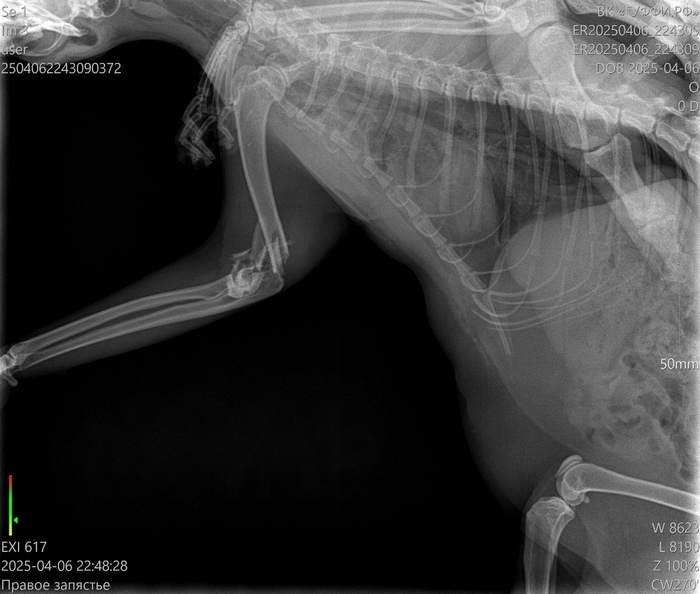

Верю, что тут есть профильные специалисты. Позавчера не уследил за кошкой, забыл закрыть форточку на какие-то полчаса, выпрыгнула с пятого этажа и крайне неудачно. Переломаны левые передняя и задняя лапы. Но если по задней лапе прогноз хороший, то по передней хирург сказал, что сустав раздроблен, и конечность он будет сращивать жестко и под углом. Кошке всего полтора года, очень жизнерадостная - даже под опиоидным обезболивающим уже сегодня сама сходила по-маленькому, и пытается встать и бегать за остальными двумя кошками (у нас их три).

Можно ли по рентгеновским снимкам определить - удастся ли сохранить подвижность лапке? Если искать хирурга, который за это возьмется.